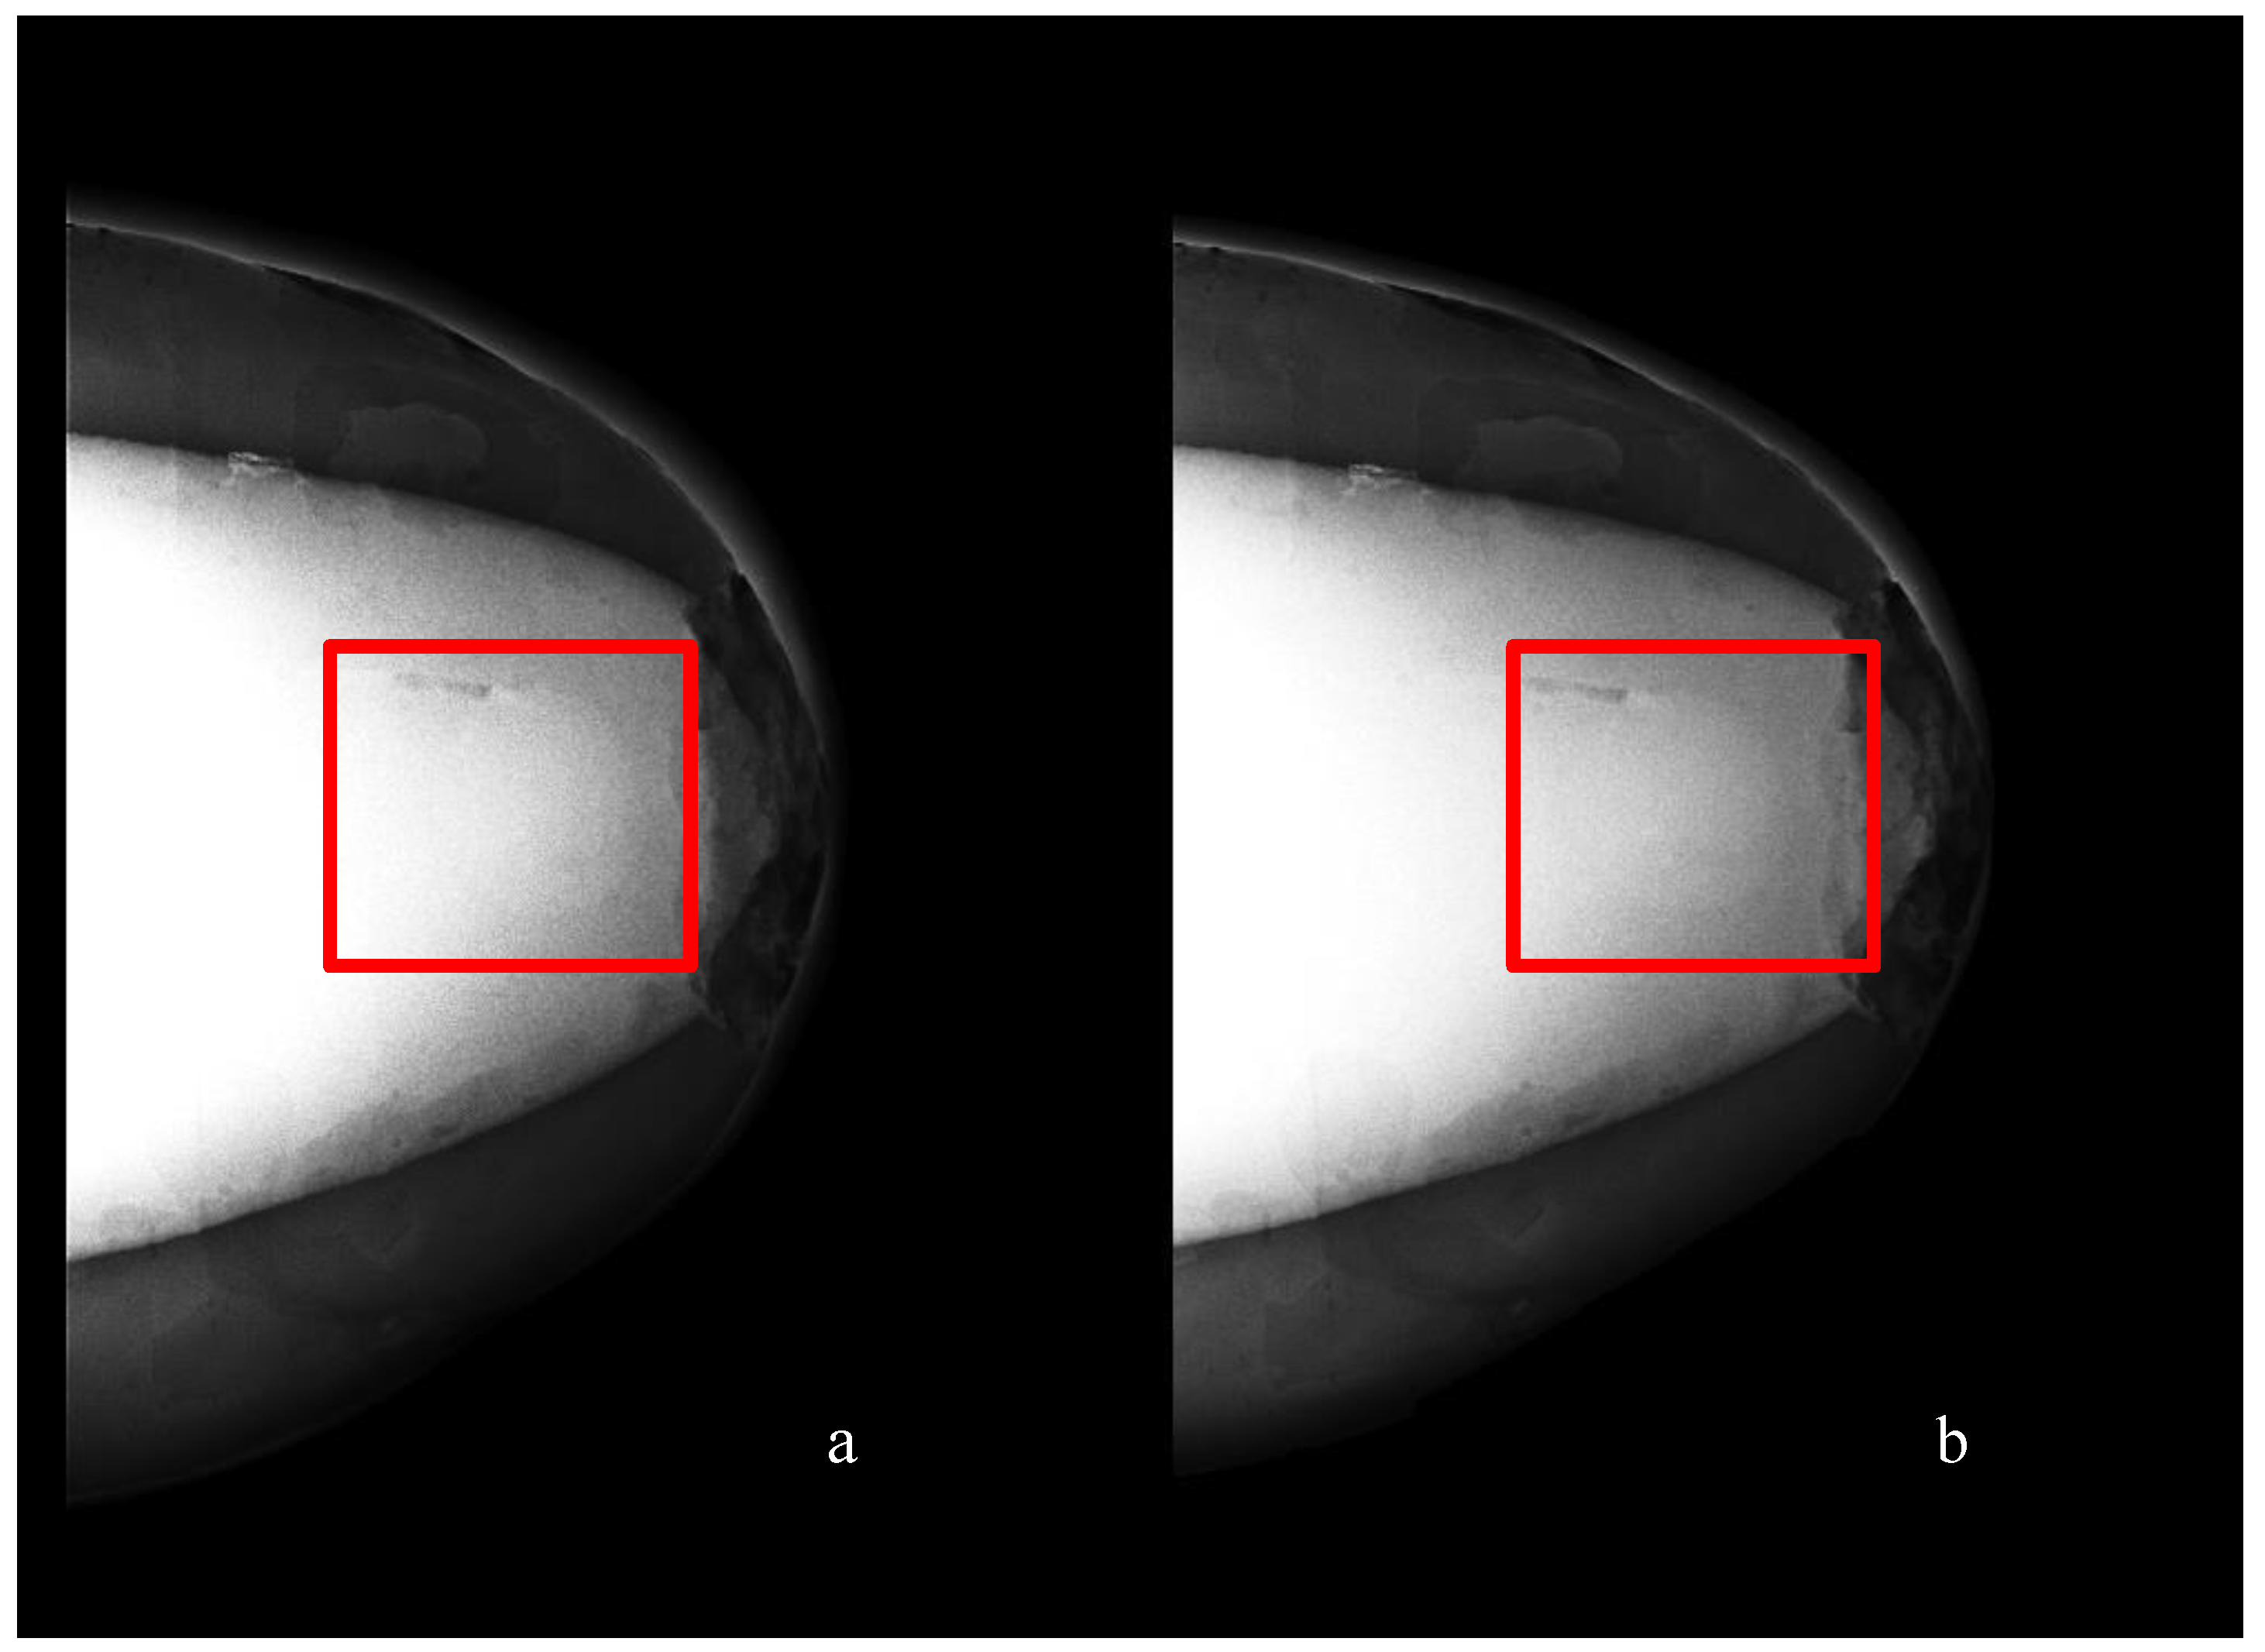

- Digital mammography scanning of Phantom A was performed with a Mammomat Novation DR system (Siemens Medical Solutions, Germany). The phantom was vertically taped to the device to reproduce the position of the breast during a mammographic exam (Figure 7). However, no compression was applied to the phantom as the fat-mimicking material was not elastically compressible. As a result, a poor contrast was observed between tumor and fibroglandular tissue. Phantom A was imaged at Mo/Rh 28 kVp and 140 mAs (Figure 8a) and at Mo/Rh 34 kVp and 160 mAs (Figure 8b), with a pixel spacing of 0.07 × 0.07 mm2, focal spot 0.3 mm and FOV 286 × 233 mm. The relative lack of contrast between the tumor and fibroglandular tissue was as a result of the lack of breast compression used during the acquisition, due to the lack of compressibility of the phantom materials. However, the relative contrast displayed between the fibroglandular and the tumor TMMs with the slightly higher kVp was slightly better. The bright external surface in each image is the skin TMM, while the darker irregular structure next to the skin is the subcutaneous fat TMM. The saturated white region is the fibroglandular tissue and the tumor mimic is within the red square; the contrast definition between both of these tissue types was challenging, which was representative of the clinical situation where dense breasts are imaged. Finally, as mentioned above, there was slightly better contrast between the fibroglandular tissue mimic and the tumor mimic with the slightly higher kVp. The same low contrast appears in the CT scanning results, performed with a Symbia TruePoint SPECT-CT scanner (Siemens Medical Solutions, Germany). The CT images were acquired at 80 kVp and 36 mAs, with a pixel spacing of 0.97 × 0.97 mm2 and slice thickness of 2 mm. In both phantoms, the tumor was localized using the MRI datasets as reference (Figure 5). Representative CT images of the phantoms are presented in Figure 9. As for the mammography images, a similarly low contrast was observed between the tumor and fibroglandular tissue. Nevertheless, the CT images demonstrated superior resolution of the internal structures, for example, showing the subcutaneous fat TMM fingers penetrating inside the fibroglandular layer.